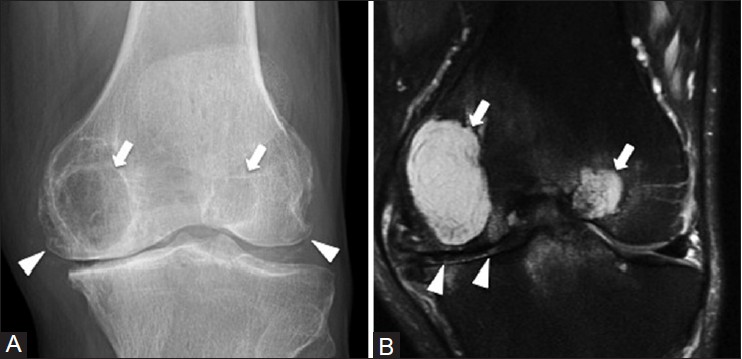

Остеосаркома коленного сустава: информация и поддержка

Раздел: Необычные решения